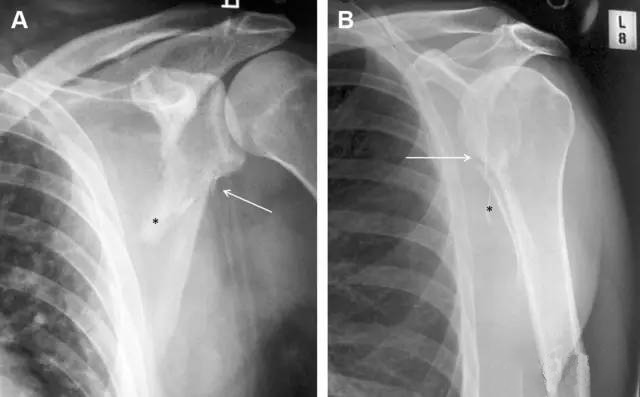

图 肩峰骨折。内旋位前后位(A)片上,骨折线几乎被喙突完全遮挡, 但是在标准前后位(B)和腋位(C)片上可见骨折线